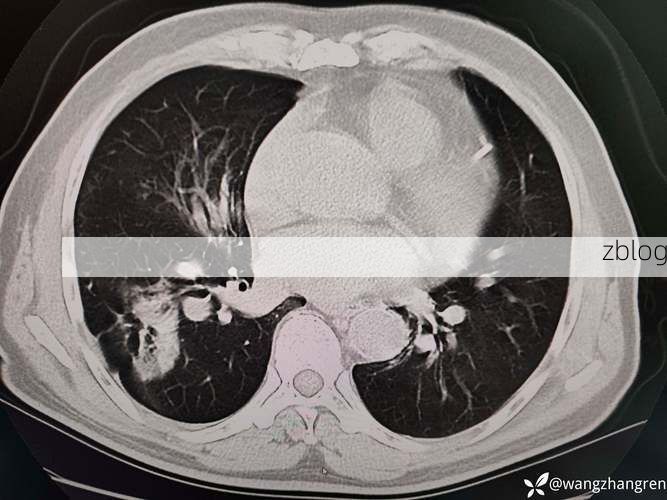

(图片来源网络,侵删)